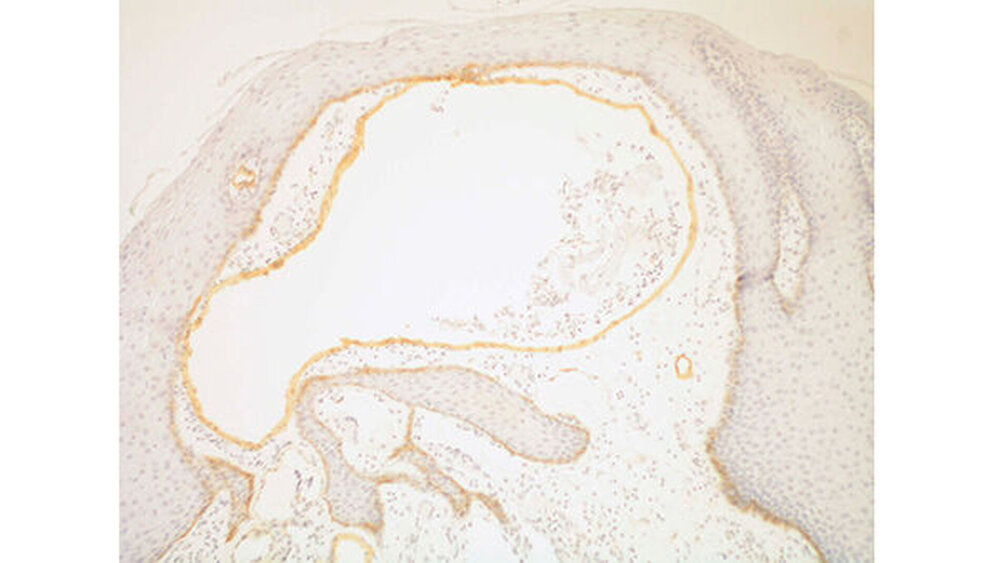

Die histopathologische Begutachtung bestätigte die Verdachtsdiagnose eines Lymphangioms mit Vorliegen von subepithelialen kavernösen Gefäßen mit typischem Endothel mit Eiweißpräzipitaten ohne Blut in den Gefäßlichtungen (Abbildungen 5 und 6). Bei einer postoperativen Kontrolle ein halbes Jahr später lagen stabile Verhältnisse vor, Schmerzen wurden von dem kleinen Patienten nicht mehr angegeben.

Histologisch zeichnen sich die unterschiedlich großen, dilatierten Lymphgefäße durch eine sehr dünne Wand aus, die durch meist abgeflachte Epithelien ausgekleidet ist. Die Lumen weisen entweder eine proteinreiche Flüssigkeit auf oder sind leer, besitzen aber nur wenig Erythrozyten. Länger bestehende Läsionen können zusätzlich interstitielle Fibrosierungen aufweisen. Anzumerken ist, dass bei kleineren Gefäßen an die Endo- thelien keine Basalmembran angrenzt und dass Perizyten fehlen [Barnes L et al., 2005; Fletcher DMC et al., 2002].